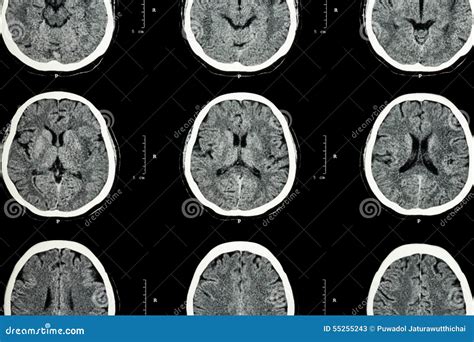

Alright, let’s dive into what a normal brain on a CT scan actually looks like. When you’re looking at these black and white images, it can seem a bit abstract, but there’s a whole lot of anatomy packed in there! We’re basically looking at slices of your brain, from the bottom all the way up to the top. The key thing to remember is that different tissues show up with varying shades of gray, white, and black based on how dense they are. Bone, like your skull, is super dense, so it shows up bright white. Areas with blood, like in the ventricles or blood vessels, can also appear white, especially if there’s bleeding. Fat and fluid, like the cerebrospinal fluid (CSF) that cushions your brain, appear darker, closer to black. Brain tissue itself, the gray matter and white matter, shows up in shades of gray. Gray matter , which contains nerve cell bodies, is generally a bit lighter than white matter , which is made up of nerve fibers covered in myelin (a fatty substance that makes them appear whiter). You’ll be able to distinguish the major structures. The cerebrum , the largest part of the brain responsible for higher-level functions, will take up most of the image. You can often see the deep grooves, called sulci , and the ridges, called gyri , on the surface of the brain. Inside the cerebrum, you’ll find the ventricles , which are fluid-filled spaces that produce and circulate CSF. These usually appear as dark, butterfly-shaped structures in the center of the brain. The cerebellum , located at the back and bottom of the brain, responsible for coordination and balance, will also be visible. And don’t forget the brainstem , connecting the cerebrum and cerebellum to the spinal cord, crucial for basic life functions like breathing and heart rate. In a normal scan, these structures will be well-defined, symmetrical, and in their expected locations. There won’t be any abnormal white spots indicating bleeding (hemorrhage) or large dark areas suggesting a stroke (infarction) or a tumor. The CSF spaces will be clear and of normal size, not compressed or enlarged abnormally. The blood vessels within the brain might be visible, especially if contrast is used, appearing as bright, branching structures. A radiologist is trained to meticulously examine every slice, comparing both sides of the brain for symmetry and identifying any subtle changes that might indicate a problem. It’s like a detailed architectural blueprint, but for your brain!

So, when a radiologist is staring at a normal brain CT scan , what exactly are they scrutinizing? It’s not just a casual glance, guys; it’s a systematic, highly trained evaluation. First off, they’re looking at the overall structure and symmetry of the brain. Is one side significantly different from the other? Are the major lobes of the cerebrum, the cerebellum, and the brainstem all present and in their correct anatomical positions? They’re checking for any signs of mass effect , which is when something – like a tumor or a large bleed – is pushing on surrounding brain tissue, distorting its shape or position. Next, they meticulously examine the ventricles . In a healthy brain, these fluid-filled cavities should be a normal size and shape, typically appearing as dark areas in the center. If they are enlarged, it could mean there’s increased pressure in the skull (intracranial pressure) due to a blockage of CSF flow (hydrocephalus) or brain swelling. If they are compressed, it might indicate a mass pushing on them. They’re also hunting for any abnormal densities . Remember how I mentioned different tissues have different densities? Well, radiologists look for unusual bright spots that could signal bleeding (hemorrhage) within the brain tissue, the spaces around the brain, or within the ventricles. Conversely, they look for dark areas that might indicate a stroke (infarction), where brain tissue has died due to lack of blood supply. Tumors will also often appear as areas with abnormal density, sometimes enhancing brightly if contrast dye is used. The skull bones are also inspected for any fractures, which would appear as sharp, white lines interrupting the smooth contour of the bone. Even subtle things like calcifications (deposits of calcium) are noted; while often benign, a significant amount or unusual location might warrant further investigation. If a contrast agent was used, the radiologist pays extra attention to how the blood vessels and any abnormal tissue (like a tumor or area of inflammation) “enhance” or light up. This enhancement pattern can provide crucial clues about the nature of a lesion. They’re essentially comparing what they see to their vast knowledge base of what a healthy brain looks like, looking for any deviation from that baseline. It’s a detailed process aimed at ensuring that everything is where it should be and that there are no hidden threats lurking within the brain’s intricate landscape. It’s all about ruling out the bad stuff to confirm the good!

So, what are the typical sights you’d expect to see, or not see, on a normal brain CT scan ? Basically, guys, a normal scan is one where everything looks as it should, with no significant abnormalities detected. You won’t find any evidence of fresh bleeding, which would show up as a bright white area (a hyperdensity) within the brain tissue or its surrounding spaces. This means no signs of hemorrhagic stroke, trauma-induced bleeding, or ruptured aneurysms. Similarly, there won’t be any large dark areas (hypodensities) that suggest a recent ischemic stroke, where a portion of the brain tissue has died due to lack of blood flow. The brain’s intricate network of blood vessels will appear healthy, with no obvious blockages or malformations visible unless contrast was used and specific vascular imaging protocols were employed. The ventricles , those crucial fluid-filled pathways, will be of normal size and shape. They won’t be squeezed or pushed aside by any abnormal mass, nor will they be excessively enlarged, which could indicate a buildup of cerebrospinal fluid (CSF) or increased intracranial pressure. The sulci and gyri , the grooves and folds on the brain’s surface, will be clearly delineated and symmetrical. If there’s significant brain swelling (edema), these features can become effaced or smoothed out, which you won’t see on a normal scan. The cerebellum and brainstem will also appear intact and appropriately located. You won’t see any tumors or lesions, which typically manifest as areas of abnormal density – either lighter or darker than the surrounding brain tissue, and potentially showing abnormal enhancement if contrast was administered. The skull bones will be intact, without any fractures. Small, age-related calcifications might be present in certain areas like the choroid plexus within the ventricles, but these are typically considered benign and normal findings. Essentially, a normal brain CT is characterized by its lack of acute pathology. It’s a snapshot confirming that the brain’s structure is sound, its compartments are functioning correctly, and there are no immediate dangers identified by the imaging. It’s the reassuring image that allows doctors to say, “All clear here!” It’s the baseline against which any future changes would be compared, making it a vital diagnostic tool for ruling out serious conditions and providing peace of mind.